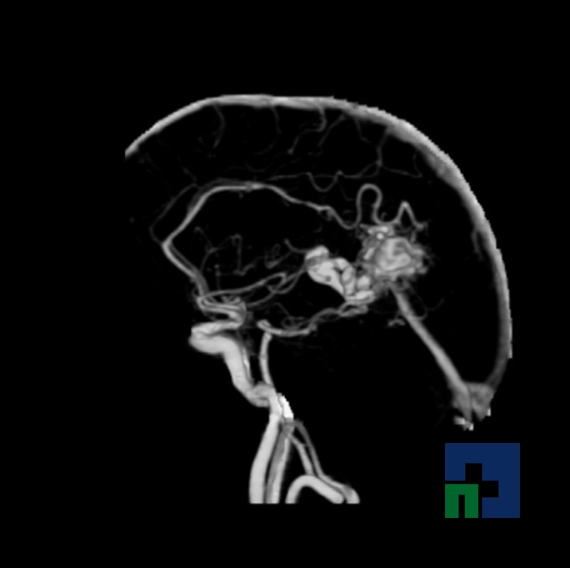

- Accidentelor vasculare cerebrale ischemice sau hemoragice

- Fistula carotido-cavernoasa